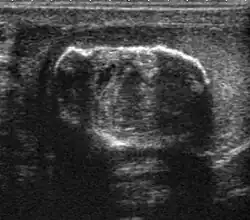

-

Fig. 29. Undescended testis. (a) Normal testis in the scrotum. (b) Atrophic and decreased echogenicity of the contralateral testis of the same patient seen in the inguinal region.